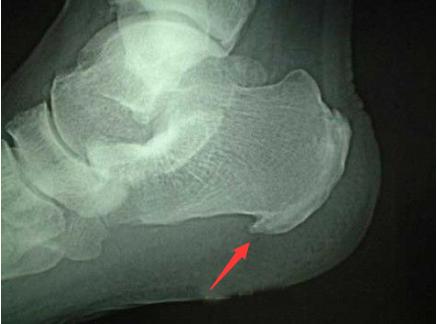

但是有的骨刺也会引起症状,比如多发于腰椎、颈椎、膝关节以及跟骨的骨刺,骨刺可能会刺激或压迫到周围的组织,引起局部的酸痛、关节的活动受限、无力等症状。